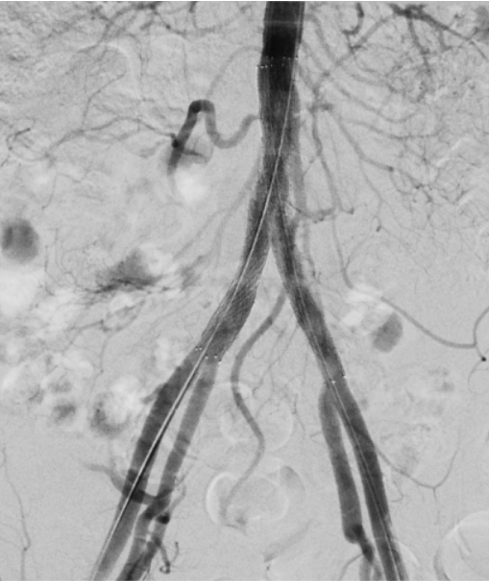

Step 1: Blocked Artery

Plaque narrows arteries, reducing blood flow and causing symptoms like poor circulation or delayed wound healing.

Step 2: Procedure

A catheter with a balloon is guided into the blocked artery. The balloon inflates, expanding the artery and restoring blood flow.